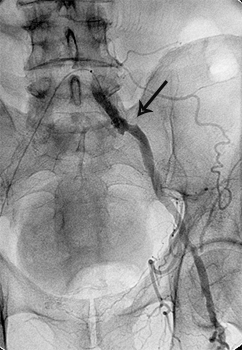

міома матки до емболізації    міома матки після емболізації

Розширена звивиста ліва маткова артерія (1),

вузол лейоміоми матки (2)

Після емболізації частками: маткова артерія

збережена (1), лейоміома не контрастується (2).